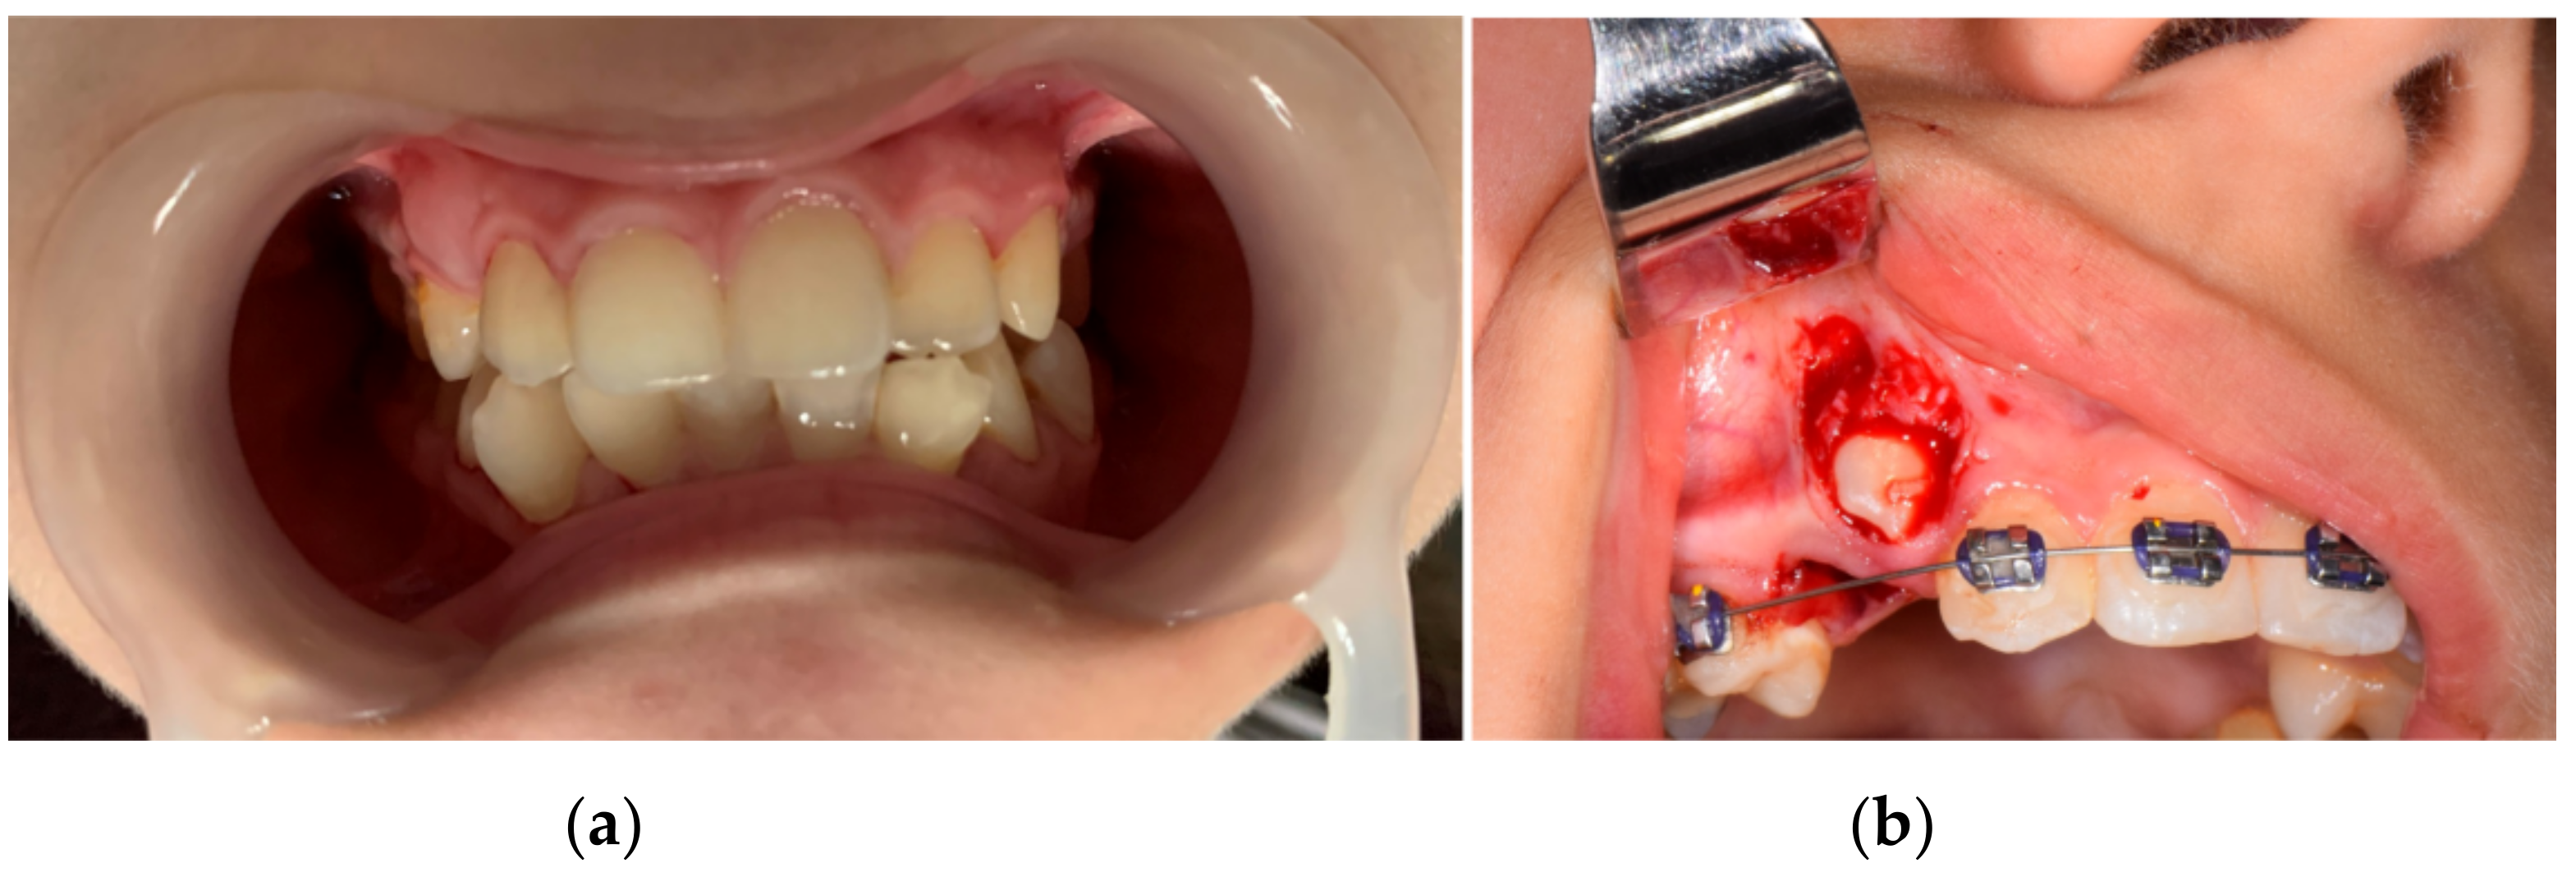

After the alginate impression of the patient’s dental arches, class III plaster models were cast. Figure 3 shows images of these models.

Figure 3. Patient’s plaster study models: (a) front image, (b) left-side image, (c) right-side image.